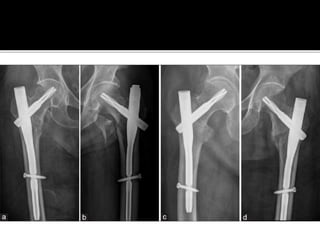

 Good reduction of the fracture, and optimal

positioning and length of the hip helical

blade are crucial to achievement of good

outcomes with the PFNA device. Further

studies are needed to compare this new

implant with extramedullary devices